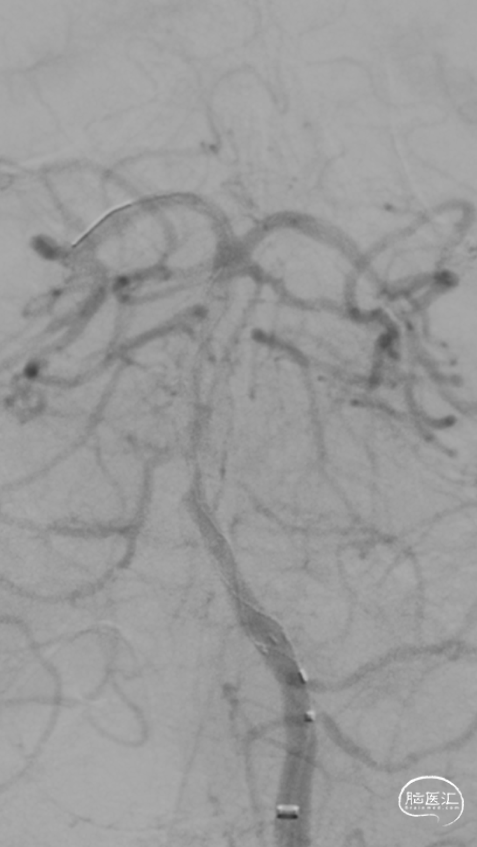

第一次取栓后,血管未通,但明确支架内狭窄位置,交换引入头端塑形的300cm 0.014in微导丝,撤出微导管,沿微导丝引入2.0mm*15mm Sprinter球囊,扩张后狭窄明显减轻,但血栓掉落至右侧大脑后动脉起始部。

交换再次引入加奇4.0mm*30mm Syphonet®取栓支架并释放。

第二次拉栓后造影,血管再通,支架内再狭窄处理风险极高,且目前前向血流3级,对比造影时影像支架未有移位。